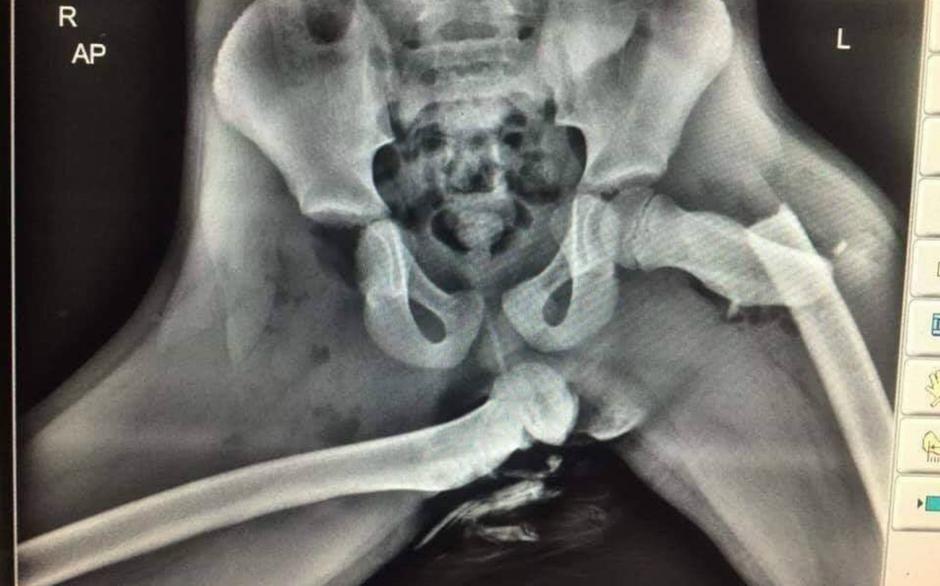

Javna agencija za varnost prometa opozarja, da med vožnjo nikar ne dvigajte nog na armaturno ploščo. Ob objavili so priložili grozljiv rentgenski posnetek osebe, ki je imela v času nastanka prometne nesreče noge na armaturni plošči.

Rentgenski posnetek noge na armaturki | Avtor: Reševalni pas/Twitter Reševalni pas/Twitter

O tem, kako nevarno je, če sopotnik svoje noge položi na armaturno ploskev v avtu, priča ogromno dogodkov in noben se ni končal kaj prida lepo oziroma neboleče.  Primer iz družabnih omrežij je dokaz, kaj lahko telesu povzroči na videz nedolžna nesreča, če imamo noge uživaško položene na armaturki. Za človeka namreč ni nevarna le nenaravna drža, temveč tudi sunek zračne blazine.